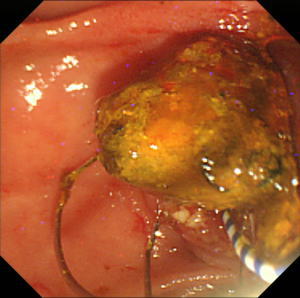

【EPLBD】 |

総胆管に15mm大の胆管結石を2個認めています(矢印)。 |

口径15~18mmの大口径拡張バルーンを用いて十二指腸乳頭(胆管の出口)の拡張術を実施しました。 |

矢印の間が拡張バルーンです。 |

乳頭拡張後に採石用のバスケット(金属線の器具)を用いて結石を破砕することなく除去しました。 |

除去した結石です。この方法では結石を破砕しなくて済むため、1回の処置でほぼすべての結石を除去することができます。 |